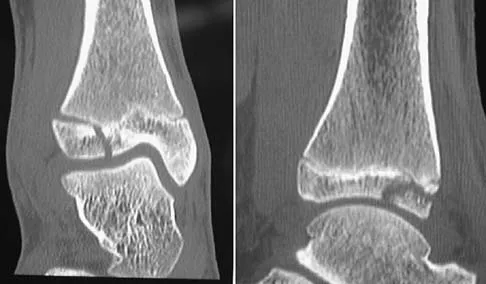

Figures 38a and 38b show the CT scans of a 64-year-old woman. What is the most likely diagnosis?

Explanation